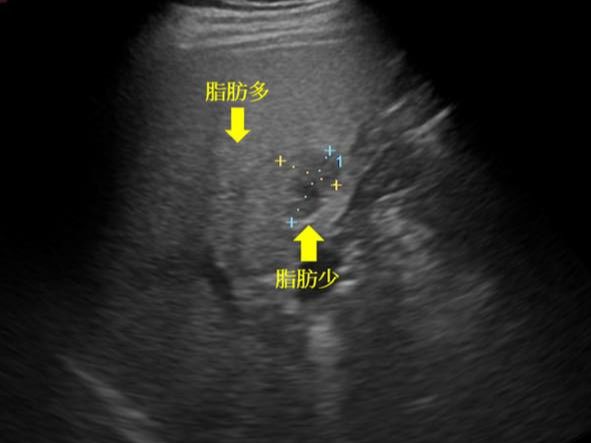

- 지방간: 지방이 간에 과도하게 축적되는 질환입니다. 초기에는 증상이 거의 없지만, 진행되면 피로감, 오른쪽 복부 불편감, 체중 증가 또는 감소가 나타날 수 있습니다. 복부 초음파로 간의 지방 침착 여부와 간의 크기 변화를 확인할 수 있습니다.